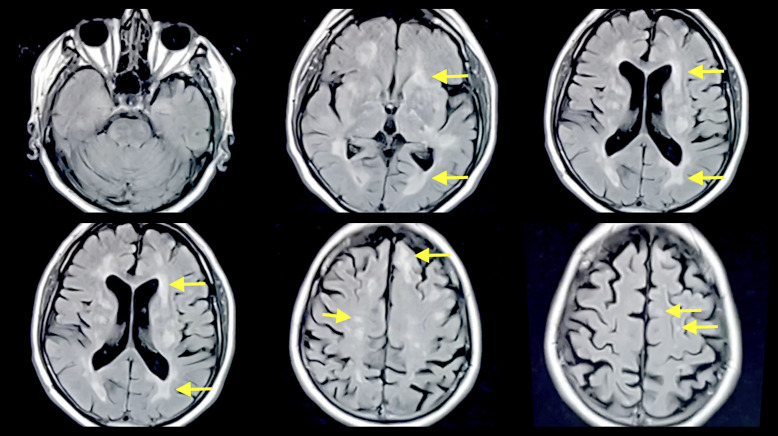

Case presentation: Multiple case reports have shown the presence of multiphasic ADEM without an established cause, emphasizing the importance of additional insight and data in this context. This is a unique case of multiphasic ADEM in a 59-year-old male with a temporal gap of 26 years with an idiopathic cause. He was suffering from many neurologic symptoms involving his upper and lower extremities and level of consciousness, and after he was diagnosed with ADEM, he was commenced on steroids and achieved a marked improvement in his clinical status.